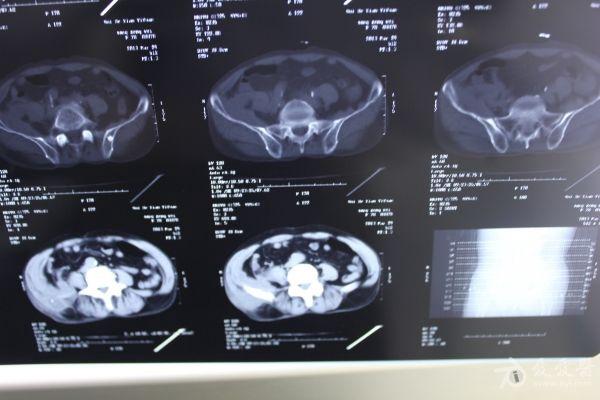

老年患者78岁,反复腰背部溃烂流脓4年,既往30年前曾在包块处排出蛔虫一条。CT: